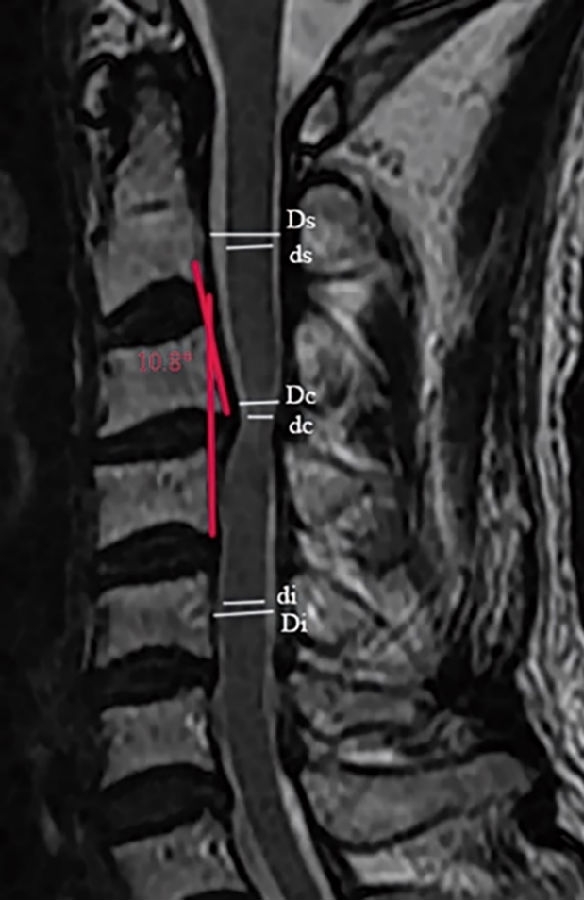

3.1颈椎MRI矢状位脊髓压迫比值

依据Fehlings等报道的方法测量颈椎MRI矢状位脊髓压迫比值(compression ratio of the spinal cord,CRS)。分别测得颈椎MRI矢状位,压迫程度最重节段脊髓直径(dc),上方椎体水平非压迫节段脊髓直径(ds)以及下方椎体水平非压迫节段脊髓直径(di)(图1)。其中选择MRI正中矢状位或旁矢状位测量,依据颈椎间盘压迫位置,分为中央型与旁中央型。CRS具体测量公式如下:

3.2 颈椎间盘突出程度

颈椎间盘突出程度依据颈椎MRI矢状位椎管压迫比值(compression ratio of the cervical spinal canal,CRCS)。椎管压迫比值CRCS与脊髓压迫比值CRS测量方法类似,只是前者测量的是椎管整体压迫程度,后者关注的是脊髓本身压迫程度。分别测得颈椎MRI矢状位压迫程度最重节段椎管直径(Dc),上方椎体水平非压迫节段椎管直径(Ds)以及下方椎体水平非压迫节段椎管直径(Di)(图1)。CRCS具体测量公式如下:

图1.颈椎MRI矢状位脊髓压迫比值和颈椎间盘突出程度的测量方法。颈椎MRI矢状位,压迫程度最重节段脊髓直径(dc),上位椎体水平非压迫节段脊髓直径(ds)以及下位椎体水平非压迫节段脊髓直径(di);压迫程度最重节段椎管直径(Dc),上位椎体水平非压迫节段椎管直径(Ds)以及下位椎体水平非压迫节段椎管直径(Di)